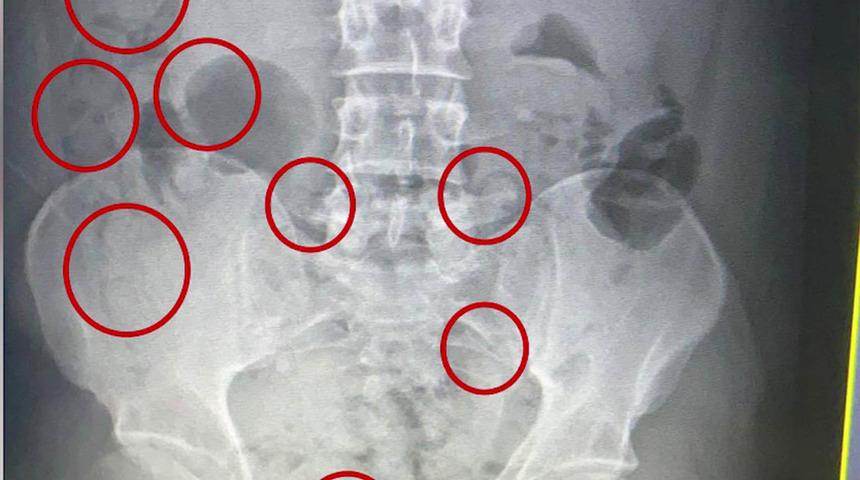

Otel odasında 9 adet kapsül halinde daralı ağırlığı 195 gram olan metamfetamin maddesi ele geçiren polis, hareketlerinden şüphelendiği kişiyi Muş Devlet Hastanesi'nde muayeneye götürdü. Yapılan röntgen çekimlerinde İran uyruklu şüphelinin mide ve bağırsaklarında yabancı cisimler olduğu tespit edildi.

Zanlının midesinden 45 adet kapsül içerisinde 305 gram, bağırsarklarından ise 54 kapsül halinde 400 gram metamfetamin maddesi çıkarıldı.